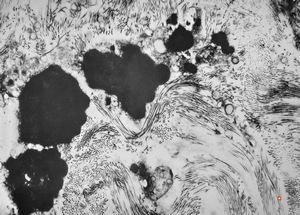

M,7y. | epidermolysis bullosa (dystrophic type) - oral mucosa